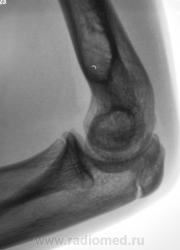

Травма. Пациент направлен на рентгенографию локтевого сустава.

Ну сломал локтевой отросток-с кем не бывает.

А, вот на пленке видно не было.

А мне не очень нравится головка и шейка луча.

а внутренний надмыщелок?

Надмыщелок, кажется, действительно отломан. А вот других повреждений не вижу.

Мы не знаем возраста пациента.Судя по зонам роста-молодой.По поводу надмыщелка-см.И.Королюка.

А. как быть с прерывистостью контура?

Там проходит ростковая зона.